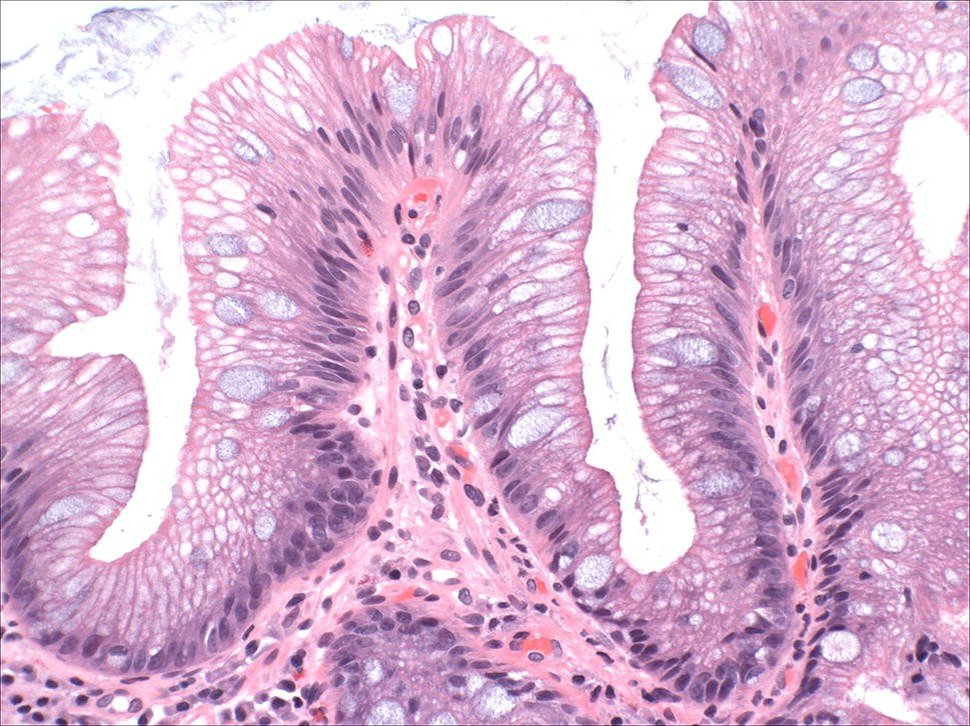

Его обширная поверхность, выстланная эпителием, сталкивается с постоянным шквалом пищевых компонентов и потенциально опасных микроорганизмов. Под этим эпителием находится самая большая концентрация иммунных клеток в организме. Бокаловидные клетки (БК) - это специализированные эпителиальные клетки кишечника, которые играют важнейшую роль в защите кишечника. Они распределены по всей эпителиальной выстилке тонкого и толстого кишечника, с заметным обилием в толстой кишке, где особенно необходим надежный слизистый барьер. Апикальная поверхность БК характеризуется наличием микроворсинок, которые значительно увеличивают площадь поверхности, доступной для секреции слизи в просвет кишечника. Эти клетки оснащены хорошо развитым эндоплазматическим ретикулумом и аппаратом Гольджи, которые необходимы для синтеза, модификации и упаковки муцинов. В их цитоплазме выделяются многочисленные секреторные гранулы, содержащие предшественники муцинов, что подчеркивает их роль в производстве и секреции слизи.

Его обширная поверхность, выстланная эпителием, сталкивается с постоянным шквалом пищевых компонентов и потенциально опасных микроорганизмов. Под этим эпителием находится самая большая концентрация иммунных клеток в организме. Бокаловидные клетки (БК) - это специализированные эпителиальные клетки кишечника, которые играют важнейшую роль в защите кишечника. Они распределены по всей эпителиальной выстилке тонкого и толстого кишечника, с заметным обилием в толстой кишке, где особенно необходим надежный слизистый барьер.

Апикальная поверхность БК характеризуется наличием микроворсинок, которые значительно увеличивают площадь поверхности, доступной для секреции слизи в просвет кишечника. Эти клетки оснащены хорошо развитым эндоплазматическим ретикулумом и аппаратом Гольджи, которые необходимы для синтеза, модификации и упаковки муцинов. В их цитоплазме выделяются многочисленные секреторные гранулы, содержащие предшественники муцинов, что подчеркивает их роль в производстве и секреции слизи. Они постоянно выделяют и обновляют слой слизи, физически отталкивая патогены от слизистой оболочки кишечника.